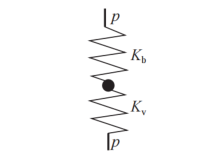

对于血液和血管的耦合系统,面对一个压力变化,我们同时要考虑血管的体积变化和血液的体积变化。而这种压力是如何被血管和血液分担的呢?考虑到血管和血液在径向上相互接触,以及我们考虑的压力变化主要在径向上,可以认为血液和血管像弹簧一样串联在一起:

血管血液耦合示意图 | 图自[6]

我们分别以s(系统,system),b (血液,blood),v(血管,vessel)的下标来标识整个系统,血液部分,和血管部分,则:

则其中

简简单单!也就是分别找到血液和血管的体积压缩模量,就可以求出系统的体积压缩模量,进而求出波速了。